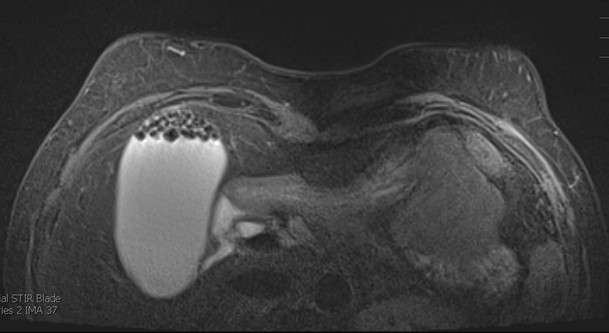

Case: Non Breast Finding Seen on Breast Imaging Figure 1

Figure 1. Cholelithiasis with mild proximal cystic ductal dilation on axial STIR imaging. Recommendation for correlation with patient's symptoms and liver function tests with consideration to right upper quadrant ultrasound versus MRCP was made.